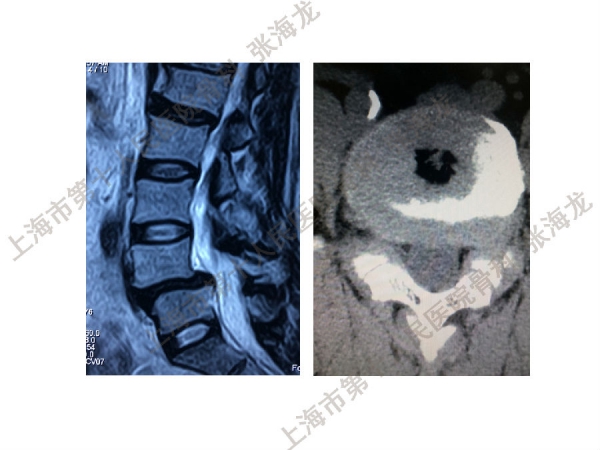

2008年3月至2010年8月,上海市第十人民医院骨科随访49例腰椎滑脱症(峡部裂型和退变型)患者,对比23例微创手术MIS-TLIF和26例开放手术治疗腰椎滑脱症的临床及影像学结果,进行了回顾性研究。

研究发现,Wiltse入路Mis-TLIF更直接的暴露峡部及关节突,对脊柱稳定性的影响较小;彻底松解辅助双重提拉复位Mis-TLIF,对于峡部裂型滑脱有较好的复位效果;对于峡部裂型滑脱,提拉复位在影像学参数上有一定优势;与原位融合相比,ODI.VAS.JOA无明显差异(样本量有限);对于退变性滑脱,单纯撑开椎间隙与原位融合可以获得较好疗效。